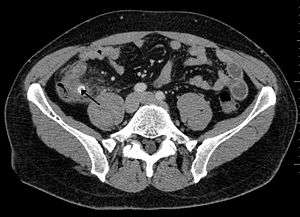

- CT Scan[2]

Appendicolith as seen on CT